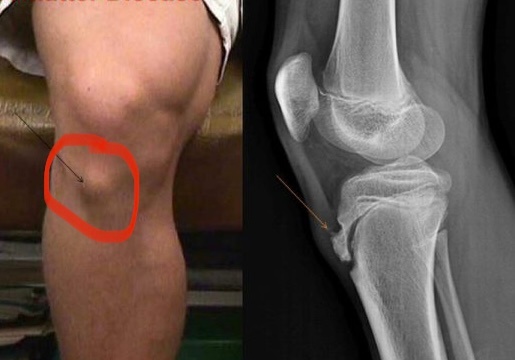

什么是胫骨结节骨骺炎 前两天有家长提问,自己孩子膝盖下方鼓出来一块骨头,还会疼痛,该怎么办?

⚠️胫骨结节骨骺炎,又称胫骨结节骨软骨病,是一种由轻微创伤引起胫骨结节骨骺的牵拉性骨突炎,好发于处于快速生长期并爱好剧烈运动的青少年,多见于12~15岁男孩,运动后疼痛及胫骨结节过度突起。

由于在11岁时会出现胫骨结节的二次骨化中心,血供来源于髌腱,当高强度运动使髌腱过度牵拉时,在胫骨结节处的髌腱产生损伤,发生无菌性炎症,引起疼痛,并且胫骨结节处发生异位骨化,从而使胫骨结节增大,形成骨性突起,也就是很多人觉得自己骨头突出来一块。